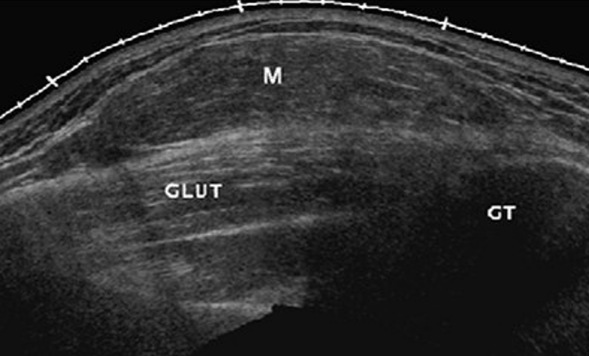

几种典型肌骨超声图片:

肌肉撕裂:为临床中较常见的疾病,主要跟运动相关。很多的时候患者可能在运动过程当中,突然感听到一个声音从前臂、小腿、大腿部位发出来;或者有的病人运动过程中自觉突然有人踢他,但并没有人触碰到他,这时患者会出现功能受限,局部疼痛等情况。